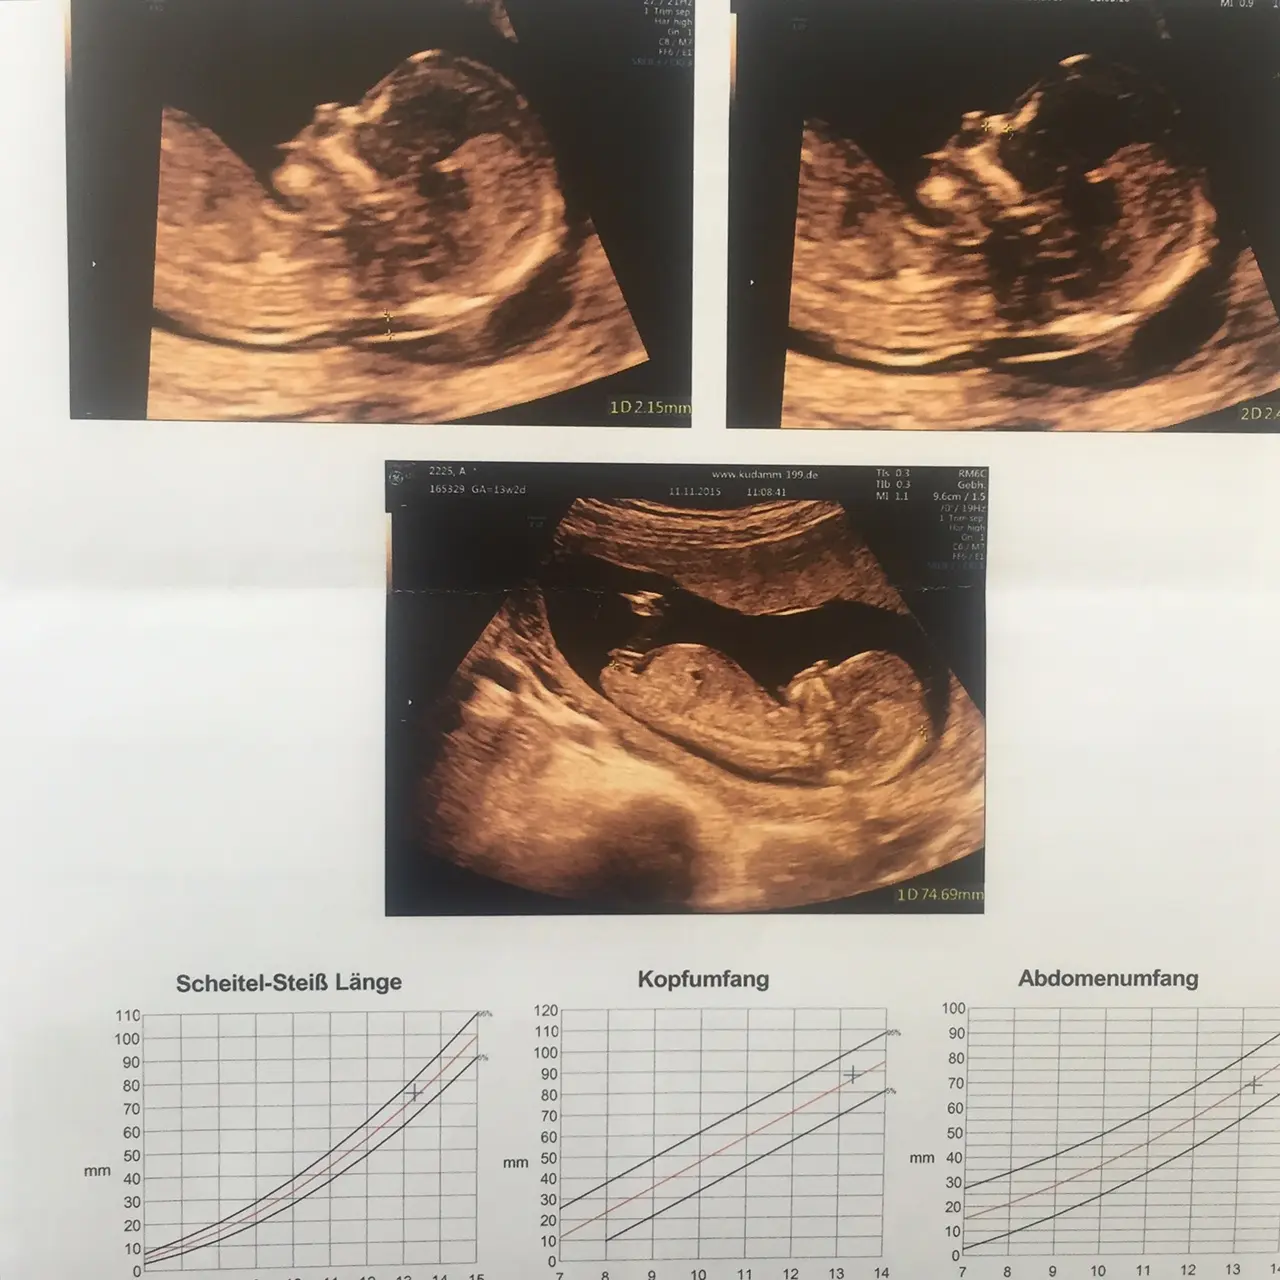

Wie funktioniert die Nackenfaltenmessung?

Die Nackenfaltenmessung wird mit einem speziellen Ultraschallgerät durchgeführt. Der Arzt oder die Ärztin misst die Dicke der Flüssigkeit im Nackenbereich des Fötus. Diese Flüssigkeit wird als Nackenfalte bezeichnet. Die Dicke der Nackenfalte ist bei jedem Fötus unterschiedlich, aber bei Föten mit bestimmten Chromosomenstörungen wie dem Down-Syndrom ist sie oft dicker als bei Föten ohne diese Störungen.

Die Nackenfaltenmessung wird in der Regel in Kombination mit anderen Tests durchgeführt, z. B. Mit einem Bluttest, der auf bestimmte Substanzen im Blut der Mutter untersucht. Diese Tests können zusammen mit der Nackenfaltenmessung das Risiko für Chromosomenstörungen beim ungeborenen Kind genauer einschätzen.